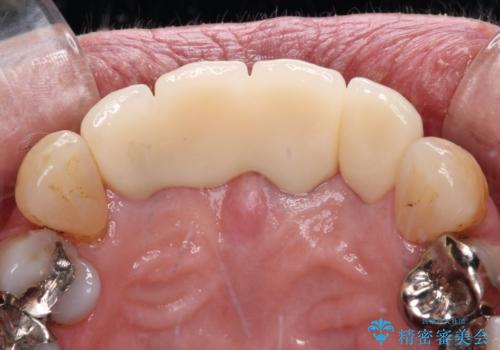

一番気になっていた隙間が埋まり、不快感から解放されました。